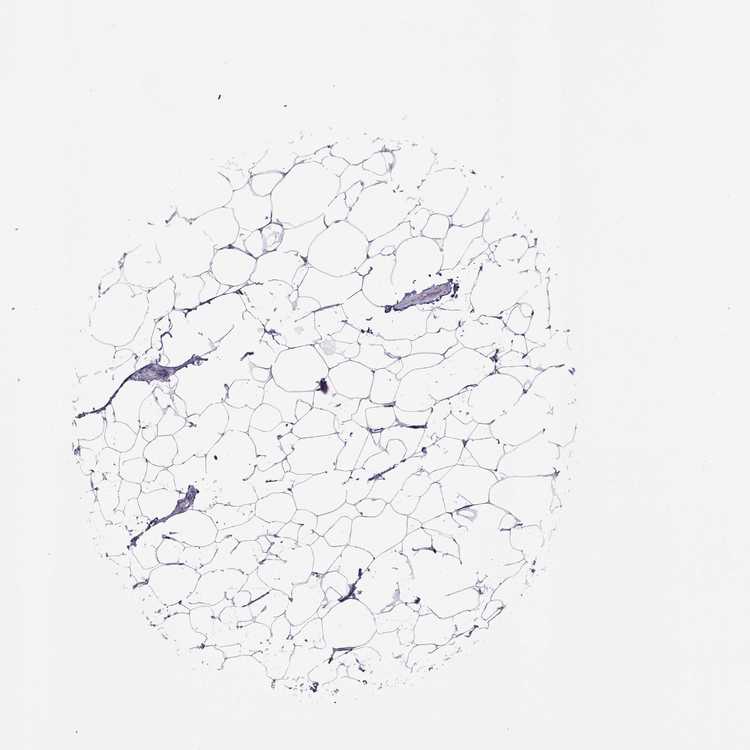

TISSUE PRIMARY DATA BREAST Show tissue menu

BREAST - Antibody stainingi

Antibody staining in the annotated cell types in the current human tissue is reported as not detected, low, medium, or high, based on conventional immunohistochemistry profiling in selected tissues. This score is based on the combination of the staining intensity and fraction of stained cells.

Each image is clickable and will lead to virtual microscopy that enables deeper exploration of all samples and also displays staining intensity scores, fraction scores and subcellular localization as well as patient and tissue information for each sample.

Antibody HPA076123Antibody HPA077266

Adipocytes Not detectedNot detected

Glandular cells LowNot detected

Myoepithelial cells Not detectedNot detected